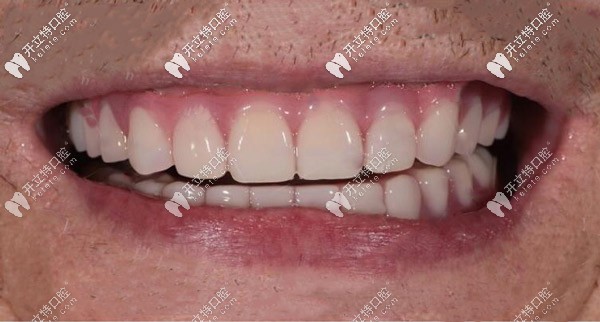

種植后▼

全口種植牙種植牙后

種植完成后口內(nèi)照片對(duì)比▼

ALL-ON-4半固定種植前后對(duì)比照

從種完牙的圖片可以看出,種植假牙比有的真牙還要好看,當(dāng)然種植牙的咬合力也是比較逼近自然牙齒的,而且有了種植體的支撐可以有效緩解牙齦的吸收。